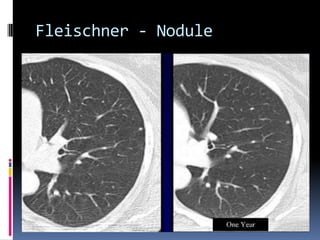

Fleischner - Nodule

Fleischner - not used when

cancer history

 Fleischner guidelines for lung nodule follow

up now include subsolid nodules.